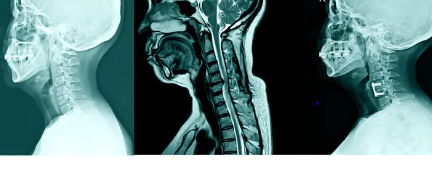

목디스크, 또는 경추 추간판 탈출증은 목의 추간판이 손상되어 인접한 신경을 압박하면서 발생하는 통증과 다른 증상들을 일으키는 질환입니다. 이는 잘못된 자세, 오랜 시간 동안의 불편한 자세 유지, 또는 외상 등 다양한 원인으로 발생할 수 있습니다. 목디스크의 치료 방법은 보존적 치료와 수술적 치료로 나뉘며, 수술은 일반적으로 다른 치료 방법들이 효과가 없을 때 고려됩니다.

수술적 치료에는 여러 방법이 있으며, 가장 일반적인 수술 방법 중 하나는 전방 경유 추간판 제거술(ACDF)입니다. 이 수술은 손상된 추간판을 제거하고, 필요한 경우 인공 추간판을 삽입하여 척추의 안정성을 회복하는 방법입니다. 또 다른 방법으로는 후방 경유 신경감압술이 있으며, 이는 신경을 압박하는 부위를 제거하여 통증을 완화하는 수술입니다.

수술은 환자의 상태, 증상의 정도, 그리고 기존 치료의 반응 등을 고려하여 결정됩니다. 수술 후에는 적절한 재활 치료가 매우 중요하며, 이는 수술의 성공률을 높이고, 환자의 빠른 회복을 돕습니다. 재활 치료는 수술 후의 통증 관리, 근력 강화, 그리고 올바른 자세를 유지하는 데 도움을 줍니다.

목디스크 수술은 전문적인 의료진에 의해 신중하게 진행되어야 하며, 수술 전에는 환자의 건강 상태, 수술에 대한 기대치, 그리고 잠재적인 위험성에 대해 충분한 상담이 이루어져야 합니다. 환자는 수술에 대한 충분한 정보를 가지고, 의료진과 긴밀히 협력하여 최선의 결정을 내려야 합니다. 목디스크 수술은 많은 환자들에게 통증 완화와 삶의 질 향상을 가져다주었으며, 적절한 경우에는 매우 효과적인 치료 방법이 될 수 있습니다.